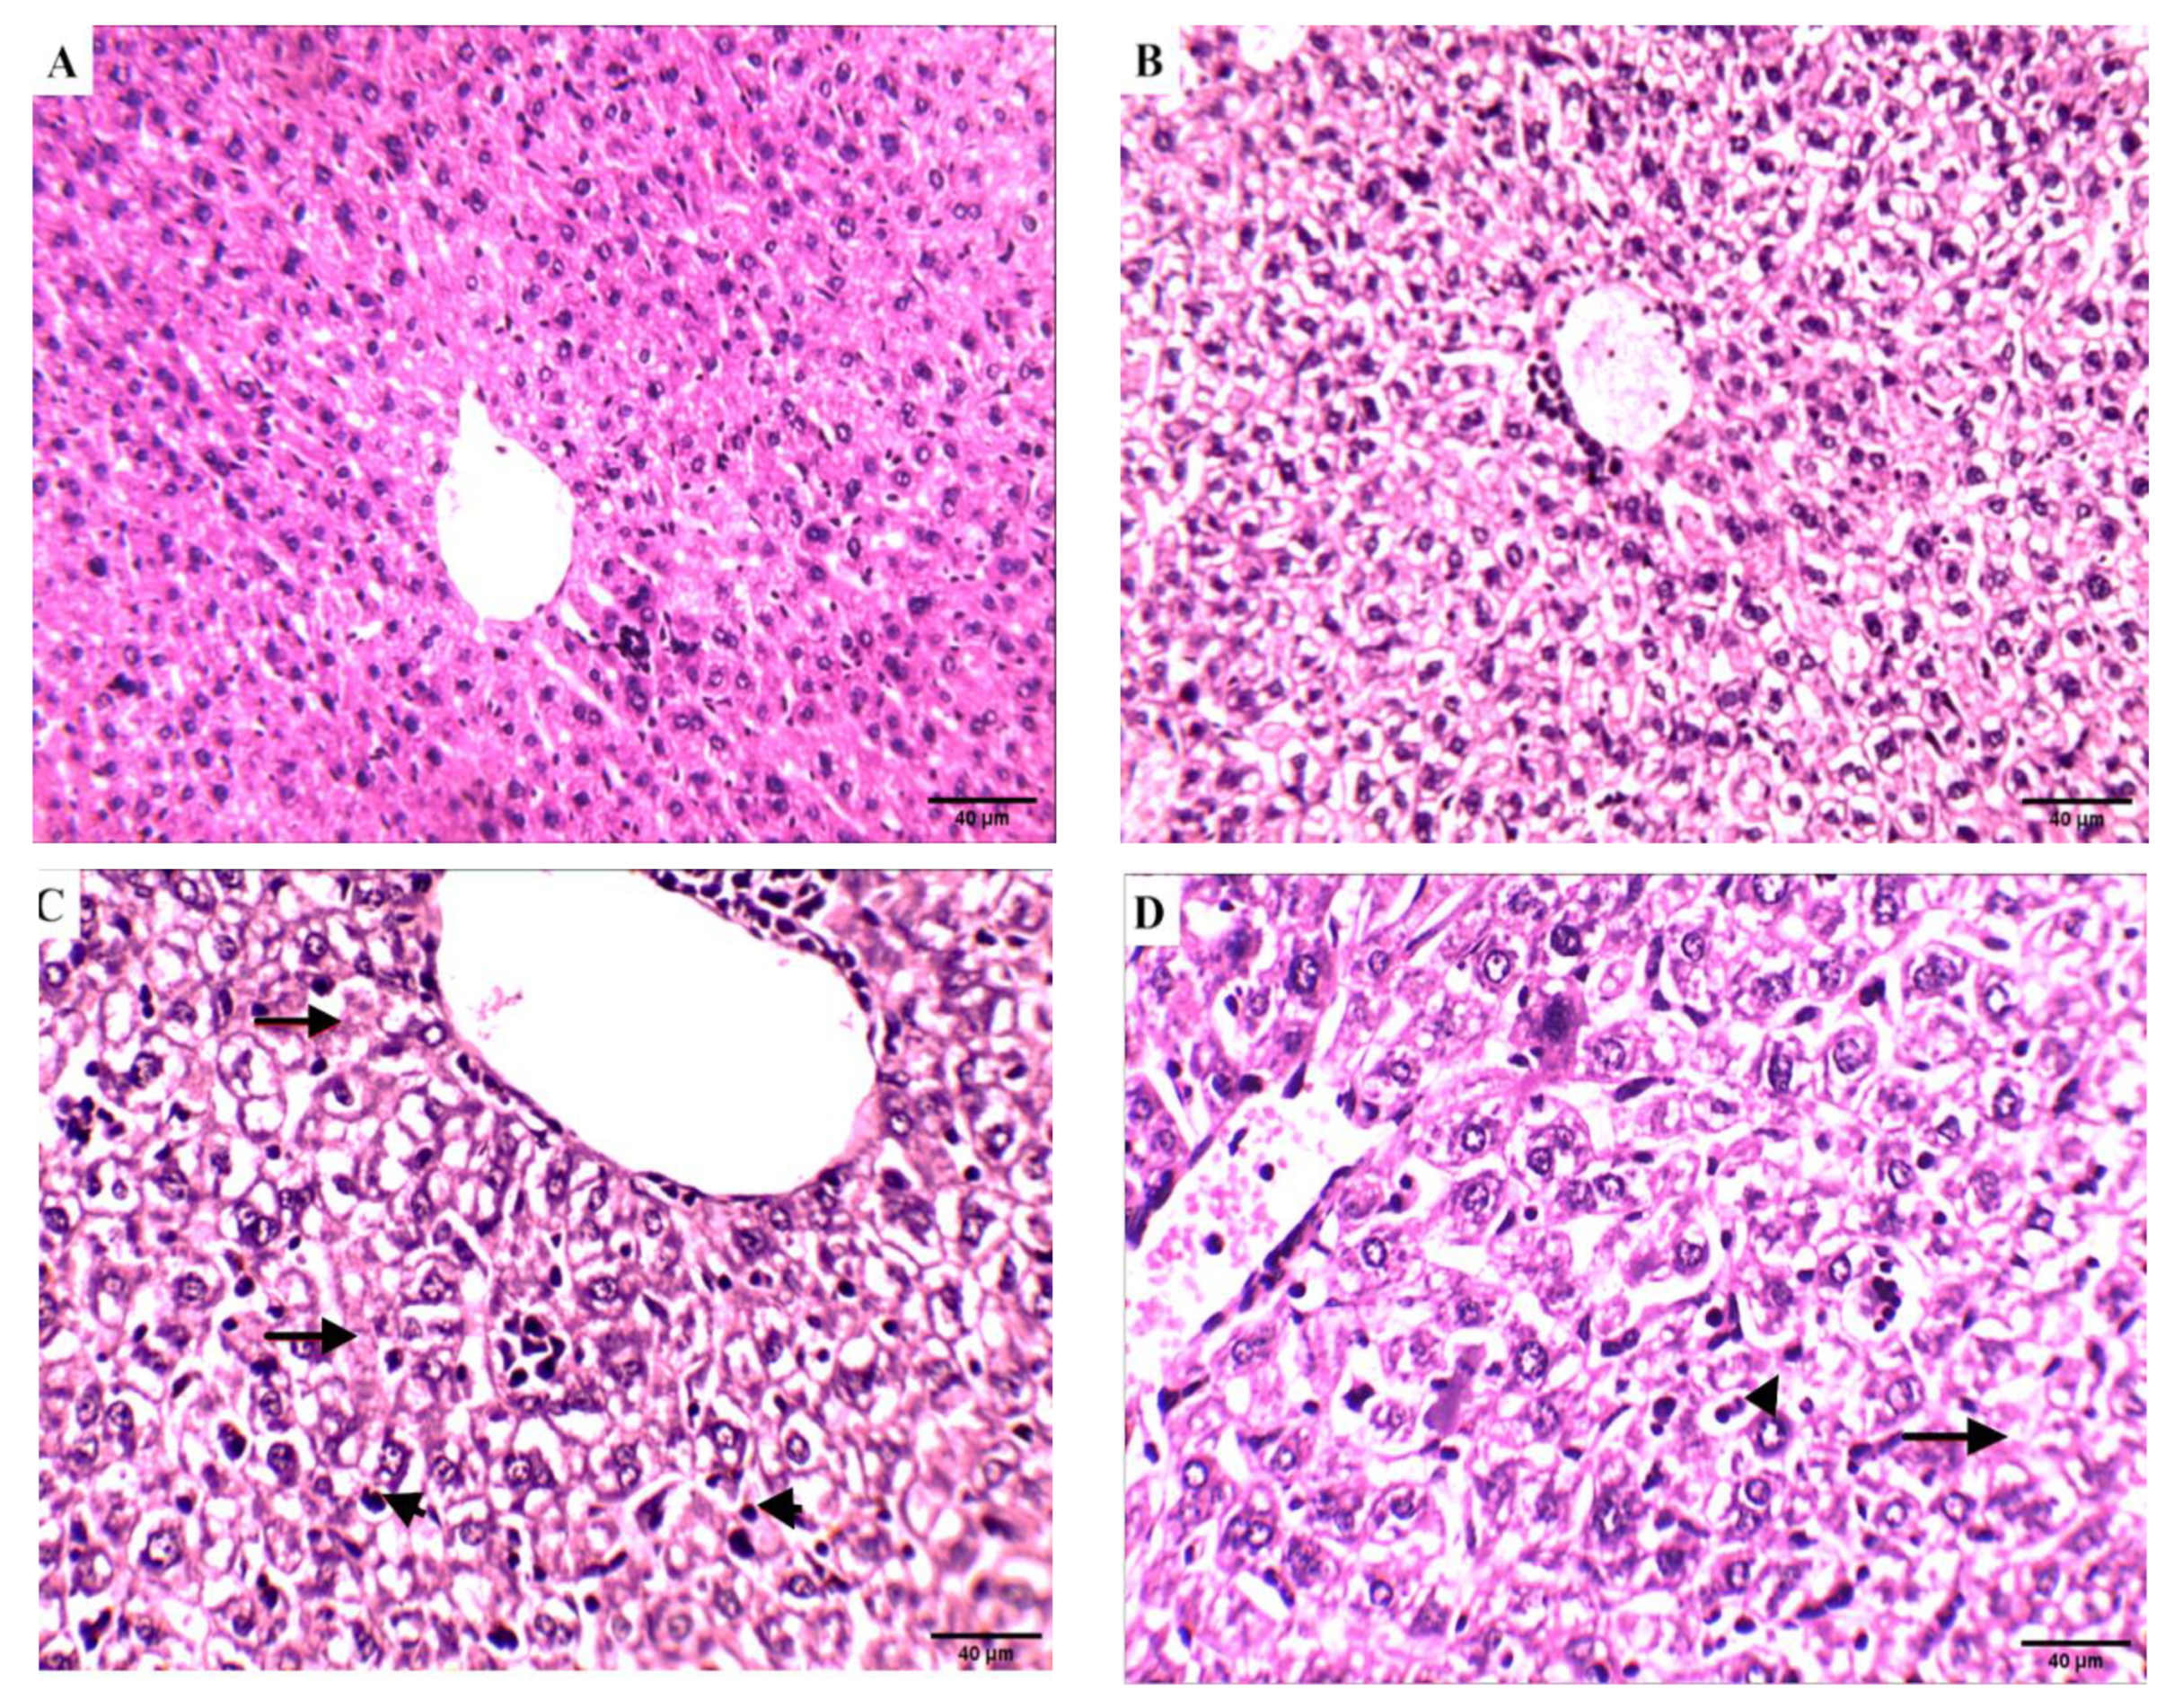

Effect of Compound 4 on the Liver Tissue of SEC-Bearing Mice

Effect of Compound 4 on the Kidney Tissue of SEC-Bearing Mice